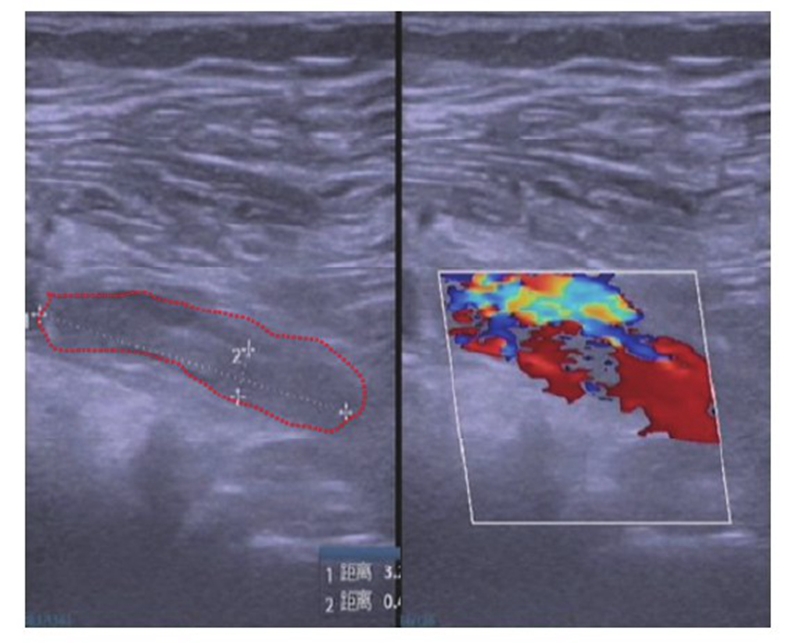

影像学检查:膝关节正侧位 X线片未见明显骨折。右膝关节MRI显示:右膝关节退行性变;胫骨平台后方骨挫伤,考虑股骨下端关节面下少许骨挫伤,考虑前交叉韧带及内侧副韧带损伤;内外侧半月板前后角Ⅱ~Ⅲ度表现,关节囊积液,关节周围软组织挫伤、肿胀(图2)。

图2 术前矢状面、横断面、冠状面 MRI示外侧半月板三度损伤